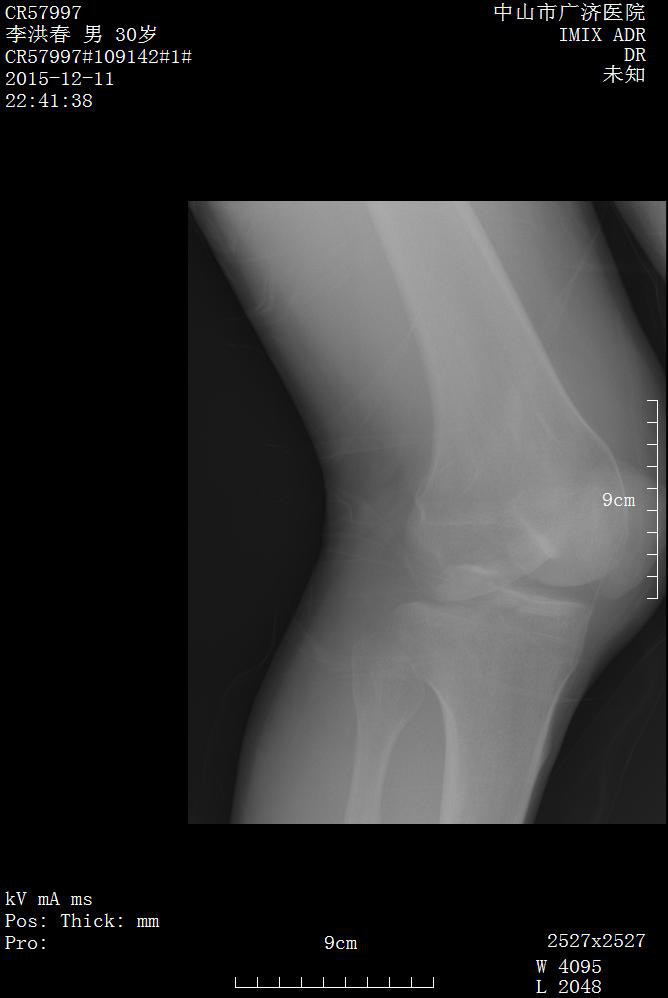

影像資料如下:

診斷:

1.右膝關節后交叉韌帶止點撕脫性骨折(2 型)

2.右髖關節脫位

3.右脛骨骨折

4.全身多處軟組織挫裂傷